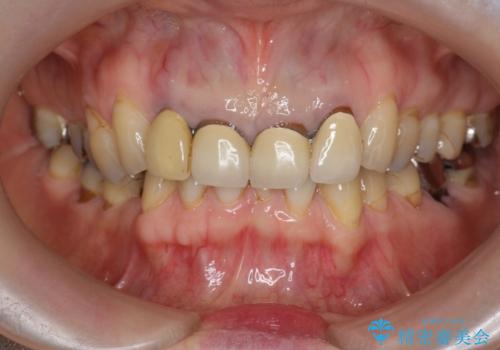

境目の見える前歯をきれいにしたい セラミック治療

- 以前治療した前歯のセラミックの歯ぐきの位置がかわってしまい境目の変色の改善を希望して来院されました。

大きな穿孔が見られた、右上側切歯の抜去をこないブリッジの設計を含めた前歯の審美性の改善を目的とするセラミック治療を行いました。